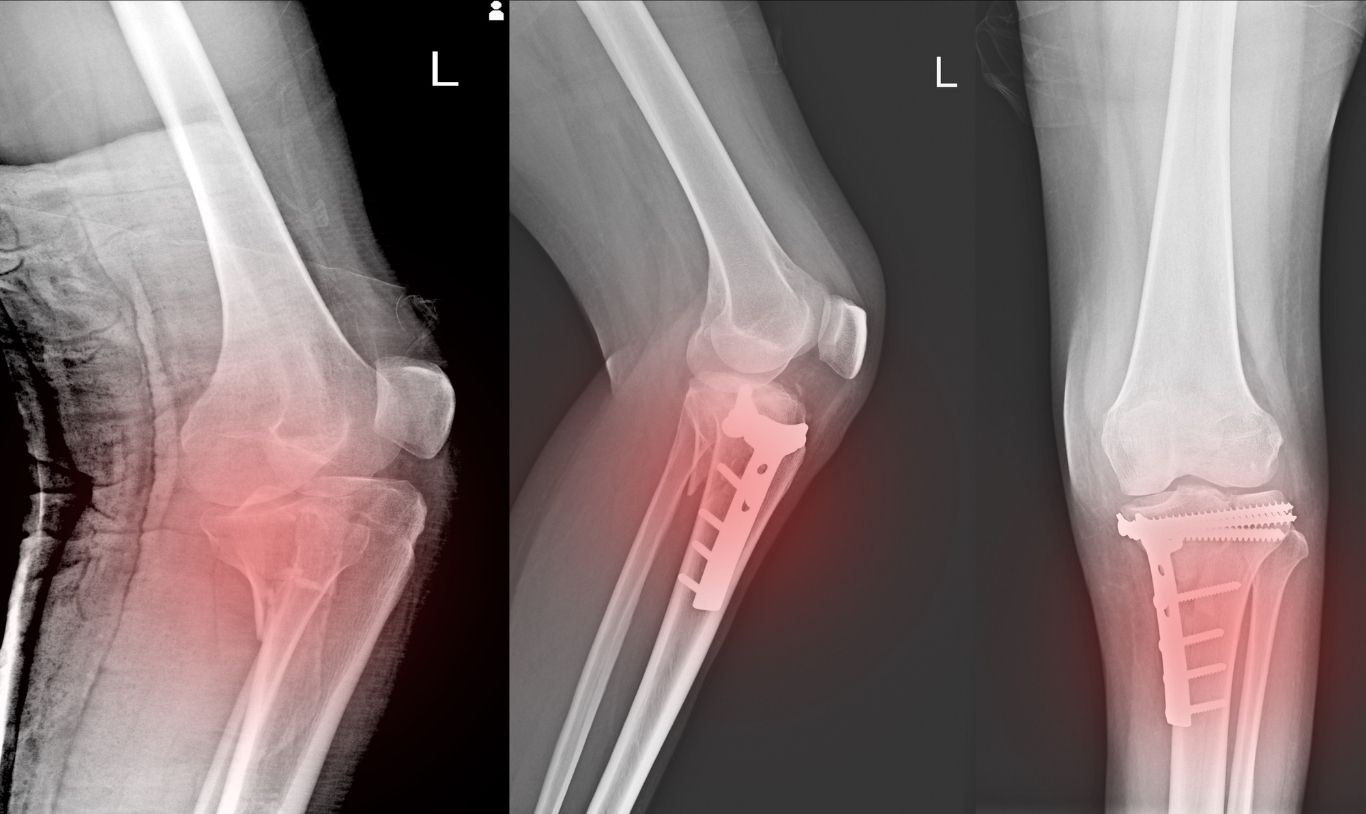

4. Knee Injuries

Rapid direction changes can lead to ligament tears (like ACL and MCL) and meniscus injuries, often requiring extensive rehabilitation.